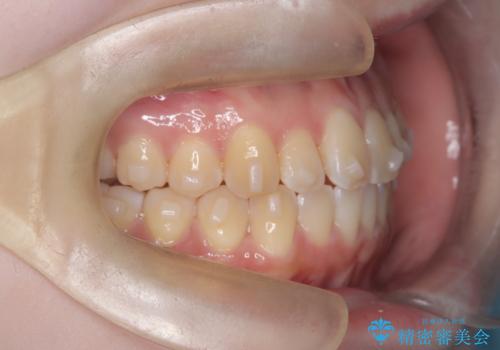

【インビザライン】オープンバイト。凸凹を治したい

- オープンバイトを主訴に来院されました。

インビザラインを用いIPRと遠心移動を行いオープンバイトと叢生の改善を行なっております。

前歯の叢生がわずかにありますが、追加アライナーの作成は希望されなかったため、歯を動かしていく動的治療は終了となりました。